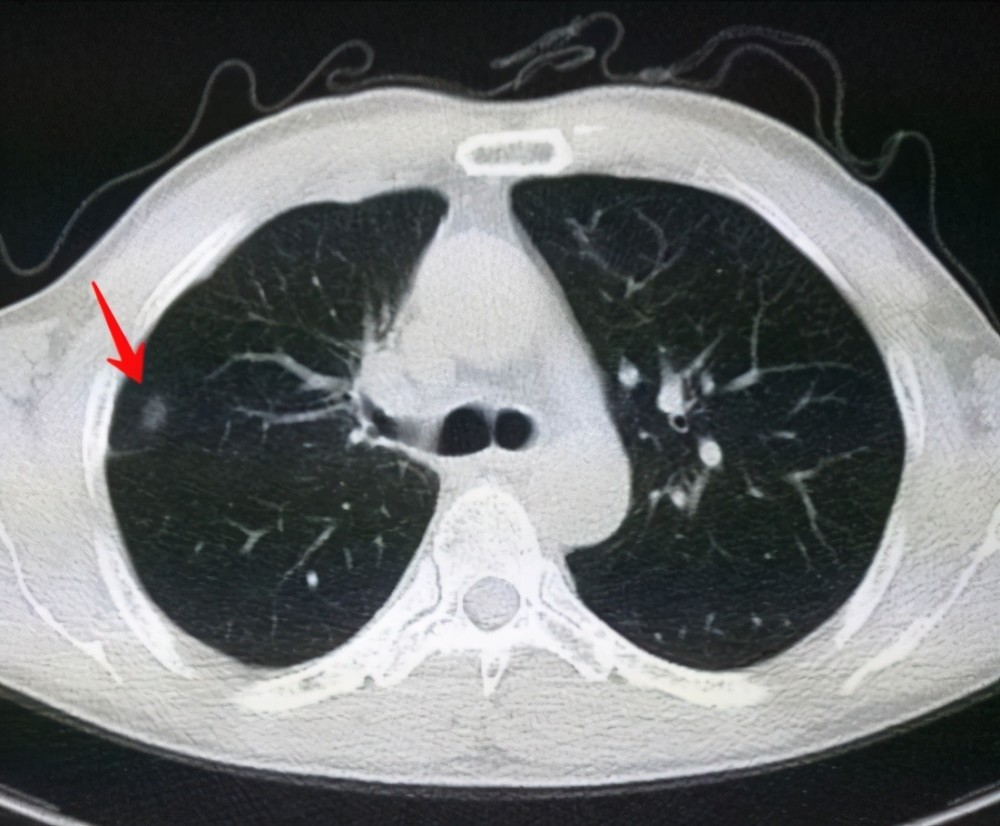

肺結(jié)節(jié)是一種常見的肺部疾病,其發(fā)病率逐年上升,雖然肺結(jié)節(jié)多數(shù)情況下是良性的,但也有可能惡化為肺癌,了解肺結(jié)節(jié)的形成原因?qū)τ陬A(yù)防和治療具有重要意義,本文將為您詳細解析肺結(jié)節(jié)的形成機制。

肺結(jié)節(jié)的形成原因

1、環(huán)境因素

環(huán)境因素是肺結(jié)節(jié)形成的重要原因之一,長期暴露于污染環(huán)境中,如空氣污染、化學污染等,可能導(dǎo)致肺部吸入有害物質(zhì),從而引發(fā)肺結(jié)節(jié),長期接觸石棉、硅塵等職業(yè)環(huán)境因素也可能增加肺結(jié)節(jié)的發(fā)病風險。